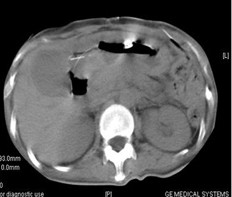

女,40歲,2006年10月底確診為胃腺癌(皮革胃),腹腔淋巴結(jié)轉(zhuǎn)移;2006年11月外科手術(shù)時(shí)見(jiàn)腹腔廣泛轉(zhuǎn)移(粘連),病灶無(wú)法切除(下圖1a,b),預(yù)期生存期低于3個(gè)月;留置(胃)造瘺管。2006年12月開(kāi)始今又生聯(lián)合化療治療,今又生2×1012VP,室溫下自行融化后加入到100ml生理鹽水中,30~40分鐘內(nèi)靜脈滴注完畢,1/次/周,連續(xù)使用6周。今又生給藥三天后靜脈化療。2007年7月外科手術(shù)拔除造瘺管;2007年9月隨訪,患者狀況良好,無(wú)復(fù)發(fā)。

1a 治療前胰腺體部和主動(dòng)脈前方淋巴結(jié)較多較大,胃底和體部較厚僵硬

1b治療后 淋巴結(jié)較少并縮小,胰腺和主動(dòng)脈之間脂肪間隙恢復(fù)清晰,胃底和體部較前變薄,柔軟

2a 治療前 主動(dòng)脈前方,胃底和脾門(mén)之間見(jiàn)大量結(jié)節(jié)狀淋巴結(jié)

2b 治療后 主動(dòng)脈前方,胃底和脾門(mén)之間淋巴結(jié)大部分消失縮小,脂肪間隙較前清晰